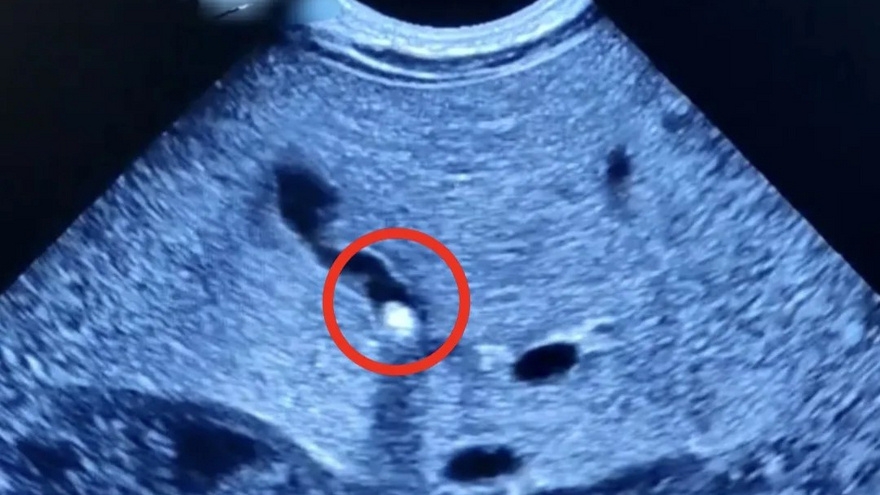

В Саратовской области у 1,5-месячного младенца обнаружили камень в желчном пузыре. Об этом случае сегодня рассказали в Балаковской городской больнице. Мама ребенка обратилась к врачу с жалобой, что малыш плохо набирает вес, а его кожа и «белки» глаз – желтые. При обследовании и выяснилось, что желчный проток частично закрыт камнем. В процессе лечения у ребенка улучшился отток желчи и началась прибавка в весе. Сейчас маленького пациента выписали на амбулаторное наблюдение. Как рассказали в учреждении, «возрастные» заболевания холецистит (воспаление желчного пузыря) и холелитиаз (наличие камней в желчном пузыре) «молодеют», то есть их начинают чаще выявлять у детей и молодежи. «За 30 лет практики это лишь второй подобный случай на моей памяти. Раньше желчнокаменная болезнь считалась заболеванием пожилых людей. Одна из причин данной патологии может скрываться в погрешностях питания мамы на разных сроках беременности. Необходимо всегда тщательно следить за рационом», – отметила замглавврач

В Саратовской области у 1,5-месячного младенца обнаружили камень в желчном пузыре. Об этом случае сегодня рассказали в Балаковской городской больнице.

Мама ребенка обратилась к врачу с жалобой, что малыш плохо набирает вес, а его кожа и «белки» глаз – желтые. При обследовании и выяснилось, что желчный проток частично закрыт камнем. В процессе лечения у ребенка улучшился отток желчи и началась прибавка в весе. Сейчас маленького пациента выписали на амбулаторное наблюдение.